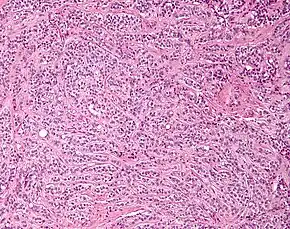

| Micrograph of a Sertoli cell tumour. H&E stain. | |

A Sertoli cell tumour, also Sertoli cell tumor (US spelling), is a sex cord–gonadal stromal tumour of Sertoli cells. They can occur in the testis or ovary. They are very rare and generally peak between the ages of 35 and 50. They are typically well-differentiated, and may be misdiagnosed as seminomas as they often appear very similar.[1]